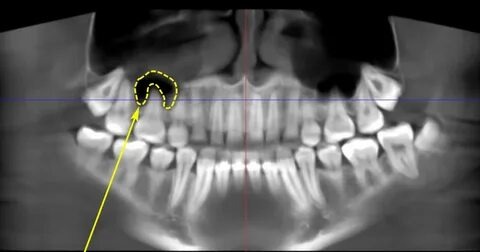

Зубы верхней челюсти располагаются близко к гайморовым пазухам. Корни верхних моляров и премоляр имеют близкое расположение к их стенкам, что делает их уязвимыми к воспалительным заболеваниям.

Врачи используют различные методы для диагностирования гайморита:

Рентген: Для оценки состояния зубов и пазух.

КТ: Для получения более детального изображения и раннего выявления проблем.